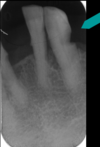

Define dilaceration

Curved root that can compromise the success of endodontic therapy or complicate extractions